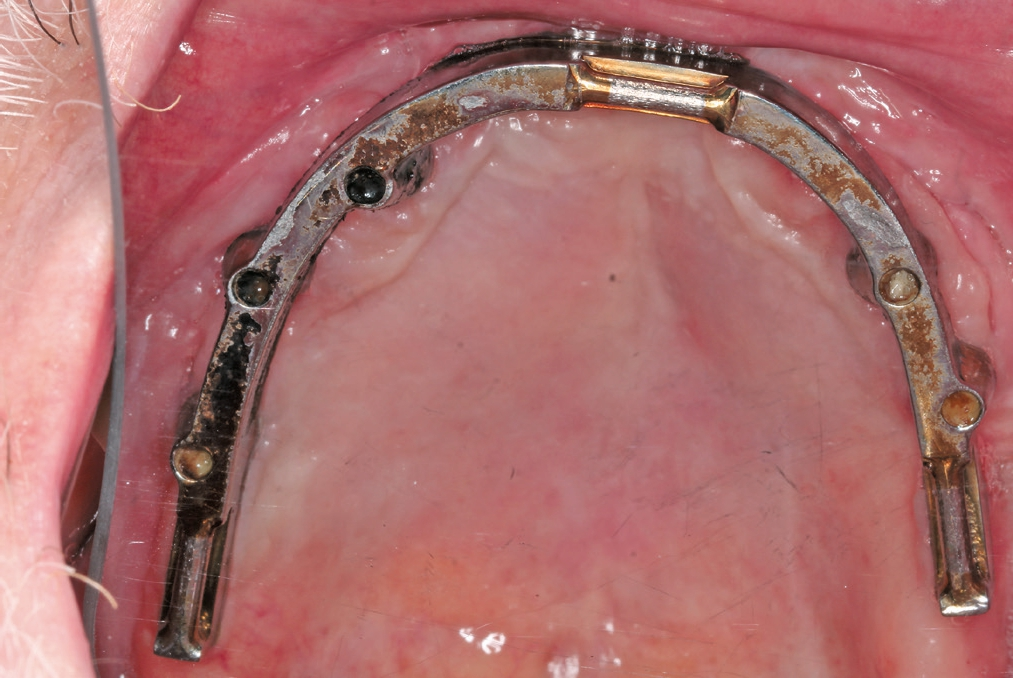

Die Transplantation erfolgte unter Vollnarkose (Abb. 7 bis 11). Für einen erfolgversprechenden Eingriff sind eine großzügige Mobilisierung des Weichgewebes, eine präzise Schnittführung und die richtige Nahttechnik wichtig. Das Freilegen des ortsständigen Knochens erfolgte über eine marginale Schnittführung von vestibulär. Danach wurde der allogene Knochenblock kurz in einer Einwegspritze unter Vakuum in steriler isotoner Kochsalzlösung rehydriert, um die Passage der einwandernden, azellulären Matrix durch Osmose zu verbessern. Die palatinale Gingiva wurde bis zur Raphe Median-Ebene deperiostiert. Das Fixieren der Blöcke erfolgte mit Osteosyntheseschrauben (Screw fixation 1.2, Stoma-System). Diese wurden schräg in das Transplantat bzw. den Knochen eingebracht, was vor allem bei einem dünnen basalen Knochen für eine sichere Fixierung wichtig ist (Criss-Cross-Technik). Idealerweise wählt man eine Schraubenposition, welche die spätere Implantatachse annähernd wiedergibt. Dies vereinfacht z. B. das Vorgehen bei der Schraubenentfernung.

Gesteuerte Knochenregeneration

Die trabekuläre Struktur des spongiösen allogenen Knochens erlaubt eine vergleichsweise schnelle Revaskularisierung. Dem Patienten wurde eine Prothesenkarenz angeordnet, was im Vorfeld mit ihm besprochen worden war. Die ersten Wochen der Einheilphase verliefen komplikationslos. Der Knochenblock aus mineralisiertem Kollagen lieferte eine stabile, osteokonduktive Leitstruktur für die Revaskularisierung und Osteoblastenmigration.

Einheilphase und Re-Entry